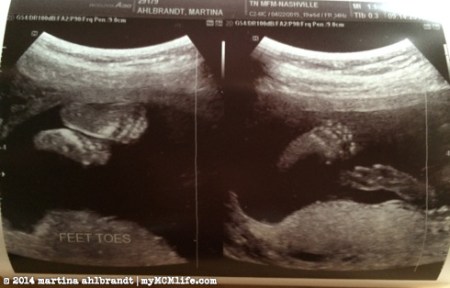

I love baby feet! (The one on the right is one foot plus some umbilical cord.)